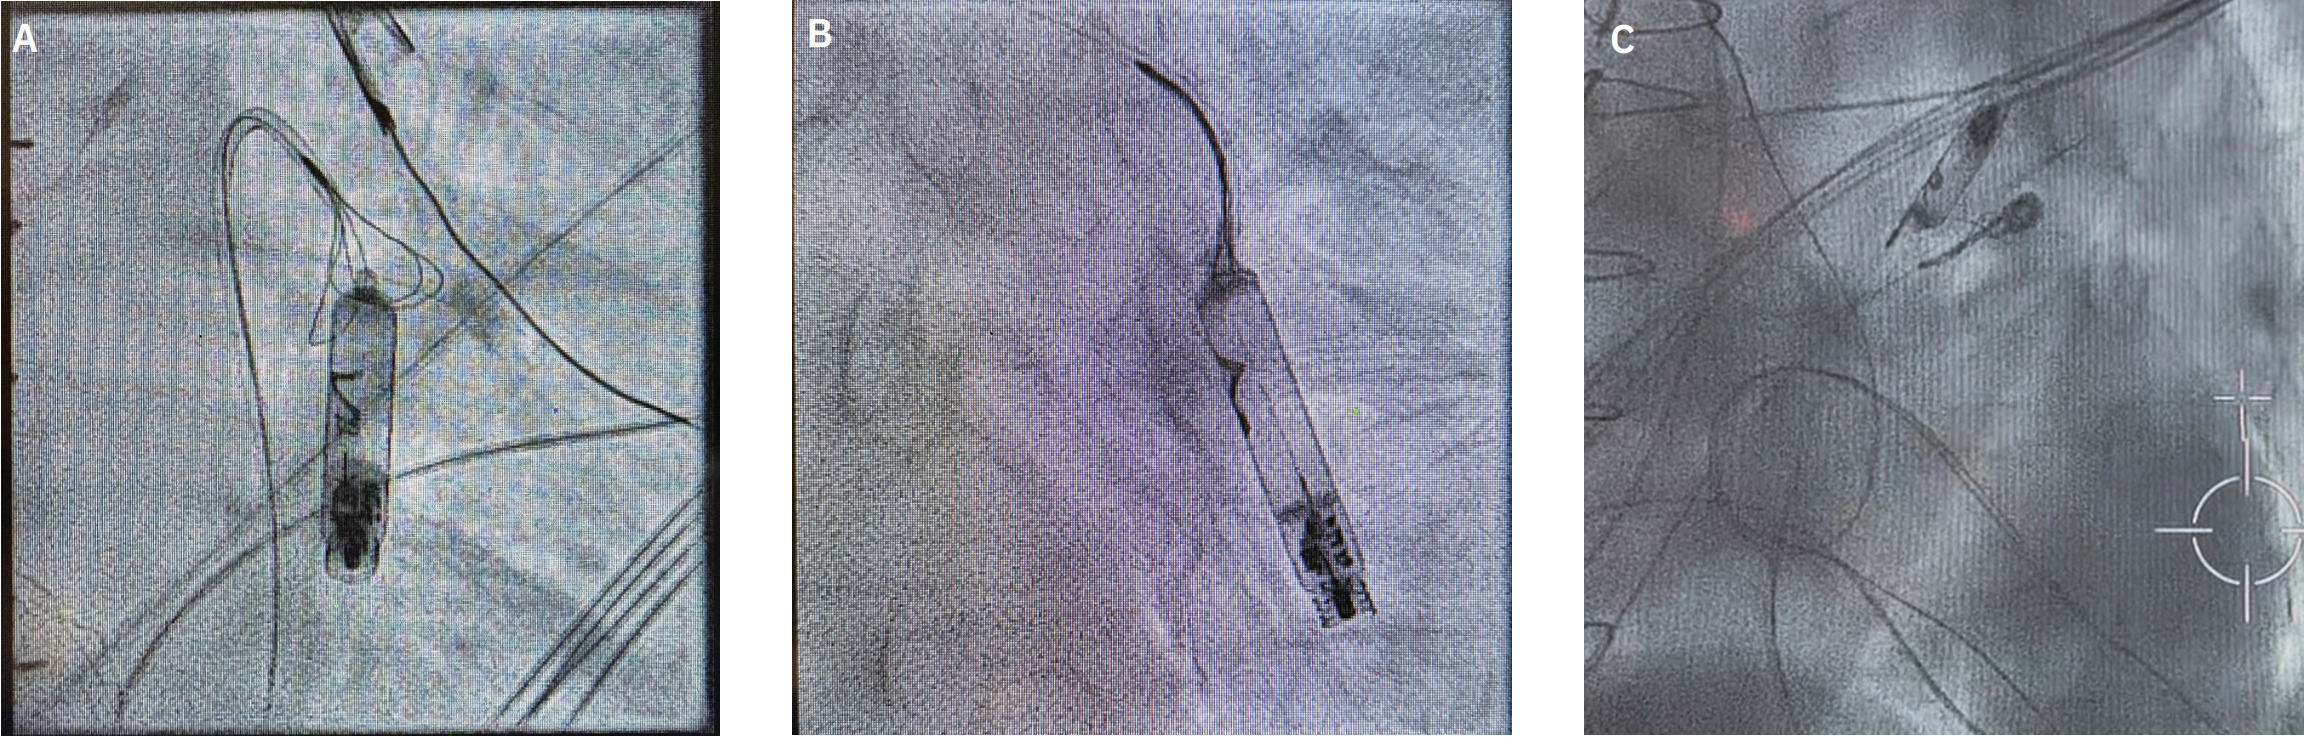

Next, a 27 French (F) AVEIR introducer sheath was placed in the RFV. A PA catheter (Swan-Ganz) was then placed through the sheath out into the left main PA. A .018” V-18 wire (Boston Scientific) was used to subselect the target branch in the posterior lower lobe. The PA catheter was removed and a 5F JR4 catheter was advanced over the .018” wire. The .018” wire was then exchanged for .035” Rosen wire (Cook Medical), over which the 5F JR4 was exchanged for a 6F JR4. Next, an EN Snare tri-loop snare (Merit Medical) was placed through the JR4 catheter and guided over the LP. The device was successfully secured and removed out of the body through the AVEIR sheath after approximately 20 minutes of procedure time. Then, a new AVEIR VR was advanced through the sheath and successfully implanted. Electrical parameters, including scrutinized current of injury, were excellent.

In this case, a PA catheter was used to access the left PA system and a guidewire was placed through the PA catheter to subselect the branch. This allowed placement of a guide catheter (6F JR4) over the wire to the site and subsequent delivery of the snare with successful retrieval.

Our team utilized the 27F introducer sheath as a workstation that allowed us to not only remove the device from the body, but also re-implant a new device in the same setting.